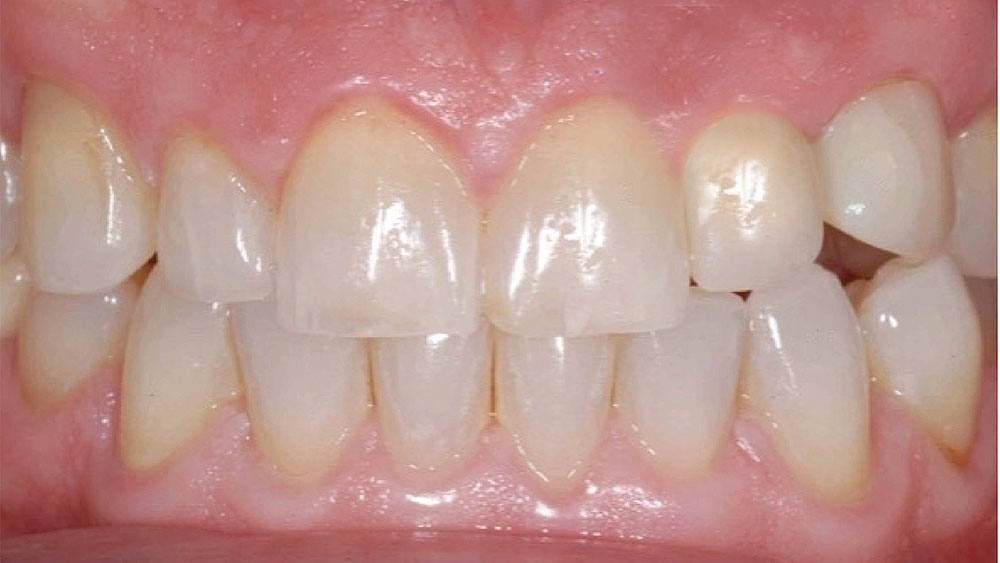

This case is an example of an ideal clinical situation for dentists who are new to placing implants in the esthetic zone. The patient requested treatment for a fractured upper lateral incisor. After extraction, grafting and healing, ample bone and soft tissue were present, and an implant was placed in optimal position for an esthetic result. The screw-retained restoration predictably restored form and function, illustrating the beautiful results that can be achieved by observing simple surgical and prosthetic guidelines.

Implant placement in the esthetic zone is well within the ability of the dentist who has mastered the posterior and is ready to expand the services offered by his or her practice. By carefully selecting and diagnosing the case, practicing restorative-driven treatment planning, and adhering to proven surgical principles, a predictable result is achieved that satisfies the expectations of doctor and patient alike.